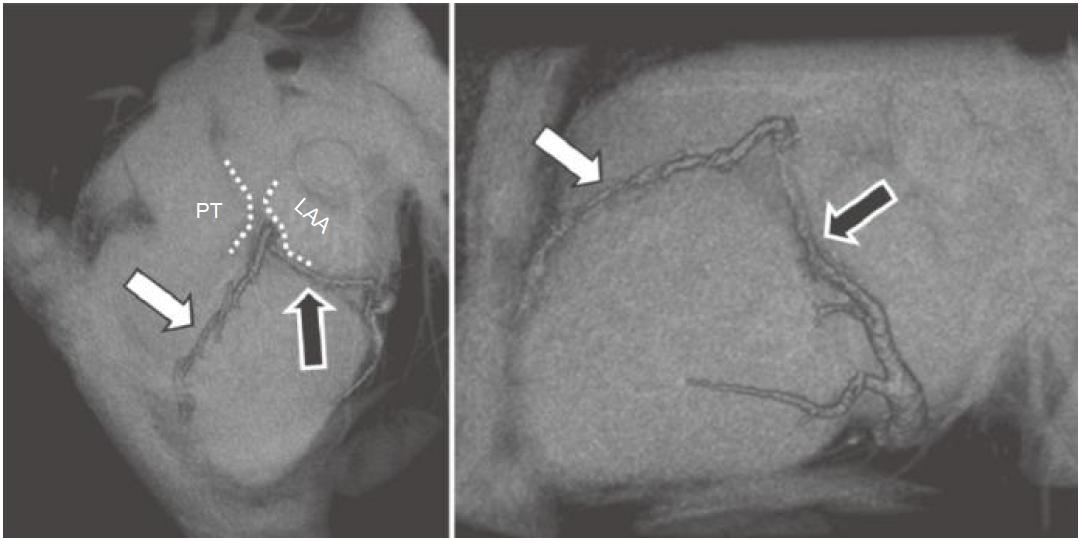

★ 心大静脉走行于左房室间沟(图13-6及图13-7)。

图13-6 前室间静脉(白箭)从心尖至心底走行于前室间沟,穿过肺动脉主干(PT)及左心耳(LAA)进入左房室沟,成为心大静脉(黑箭)

(四)前室间静脉

★ 前室间静脉起源于前室间沟,通常位于心尖部(图13-6)。

★ 尽管前室间静脉通常走行于肺动脉主干与左心耳之间,但在其离开前室间沟的位置常见变异。

★ 前室间静脉从左侧进入左房室间沟后,成为心大静脉。

★ 前室间静脉接收来自左心室远端的静脉血流。